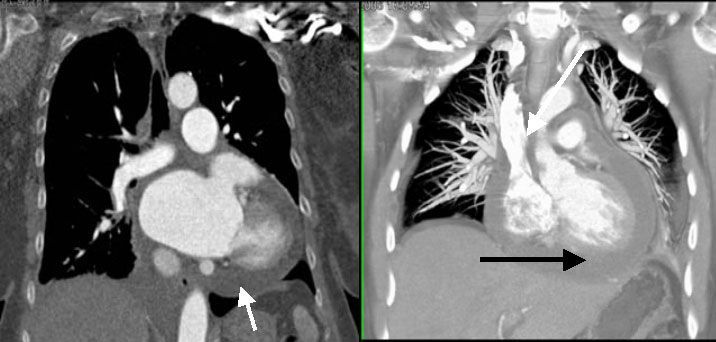

Экссудативный или рестриктивный перикардит или подозрение на заболевания перикарда, в том числе при воспалительных поражениях миокарда - тоже находятся в области применения 64 МСКТ [2] (рис№ 29,30).

![]() |

| Рис.29-30. Экссудативный перикардит, выпот (стрелки). |